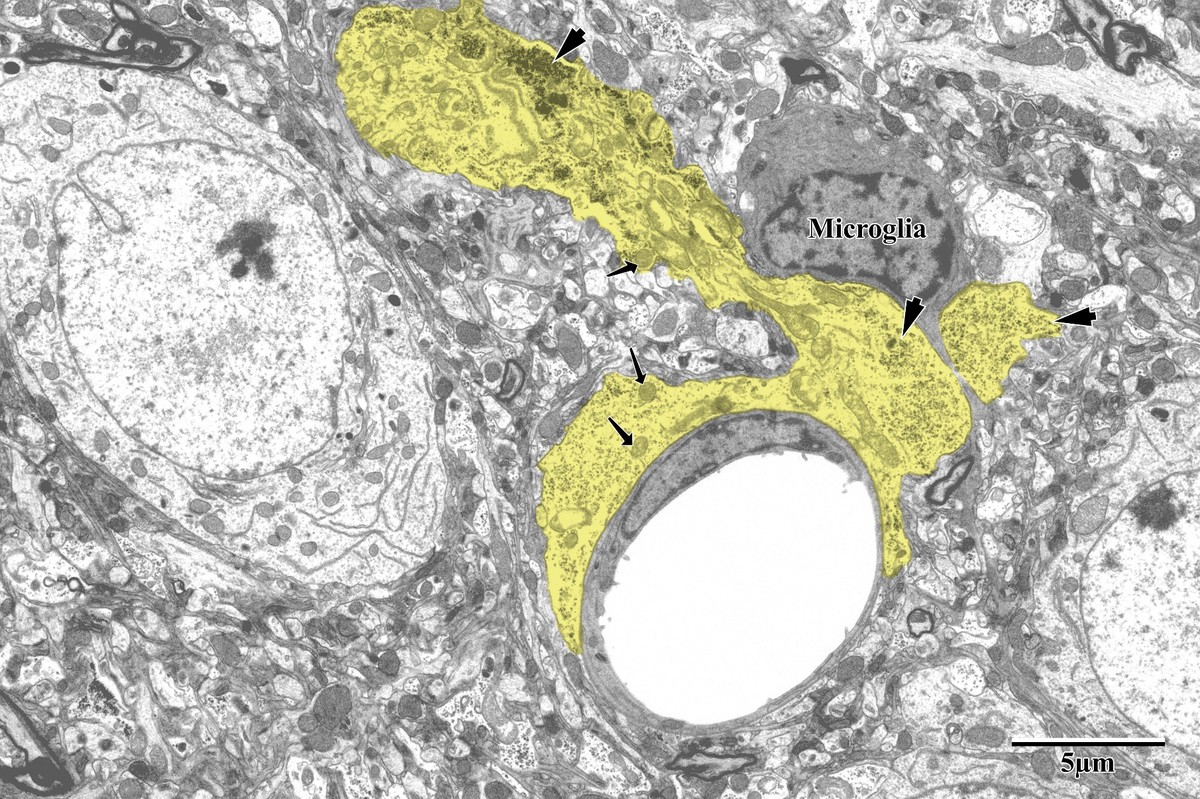

Astrocytes responded dramatically to ischemic injury, showing increased process area and reactive morphology in the peri-infarct zone. Astrocytic processes were traced and pseudocolored yellow for quantification, revealing glycogen granule accumulation, swollen mitochondria, and extensive perivascular endfeet coverage around capillaries.

Astrocytic endfeet around capillary with microglia

Astrocytic endfeet (yellow) surrounding a capillary in the peri-infarct zone. Lighter mitochondria (arrows) and glycogen granules (arrowheads) are identifying features. Microglia visible in close proximity, suggesting active inflammation. From Bayati, BSc Honours Thesis 2018.